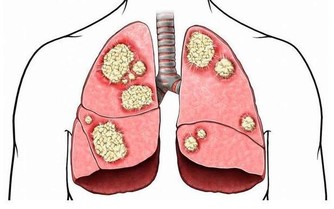

用熱水泡腳,特別是用生薑或辣椒煎水洗腳,可較快地擴張人體呼吸道黏膜的毛細血管網,加快血液循環,

從而使呼吸道黏膜內血液中的白血球及時地消滅侵襲人體的細菌和病毒,使人體免受感染。